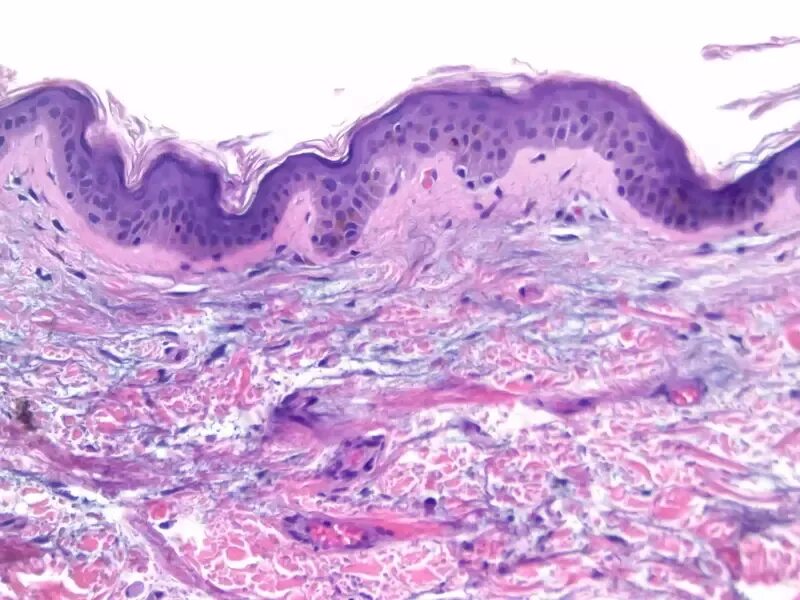

Срочные гистологические исследования